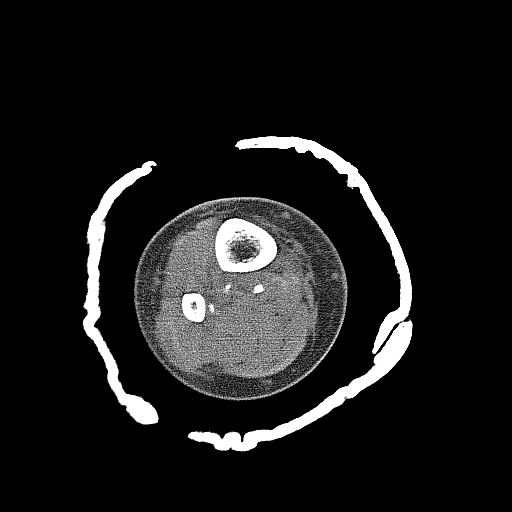

Selezione di sezioni CT di un arto inferiore fratturato